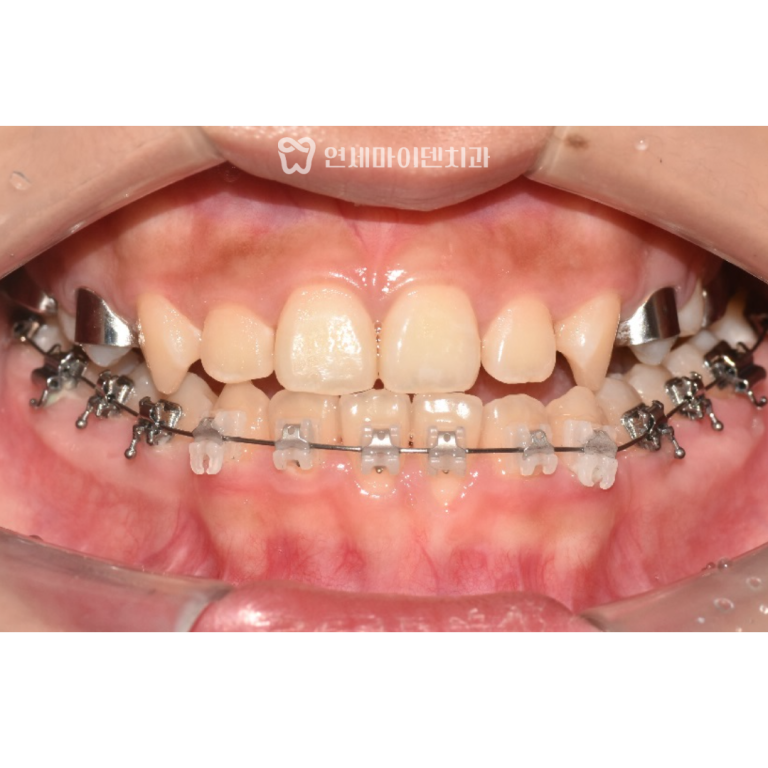

안녕하세요, 소중한 치아를 지키는연세마이덴치과입니다. 이번 증례는 심한 부정교합과 덧니가 있던30대 환자분의 비발치 교정 케이스입니다. 좁은 악궁을…